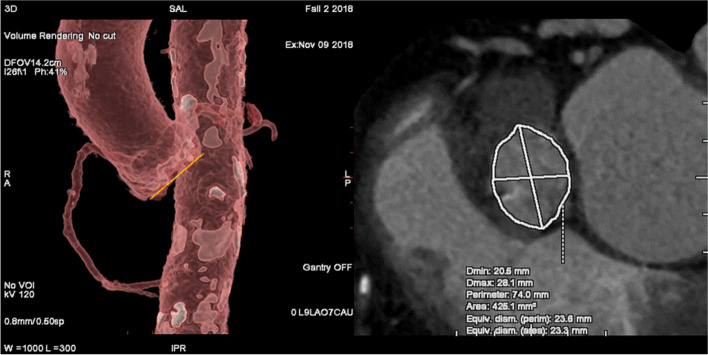

Background: Semi-automated software is essential for planning and prosthesis selection prior transcatheter aortic valve replacement (TAVR). Reliable data on the usability of software programs for planning a TAVR is missing. The aim of this study was to compare software programs 'Valve Assist 2' (GE Healthcare) and 3mensio 'Structural Heart' (Pie Medical Imaging) regarding usability and accuracy of prosthesis size selection in program-inexperienced users.

Methods: Thirty-one participants (n = 31) were recruited and divided into program-inexperienced users (beginners) (n = 22) and experts (n = 9). After software training, beginners evaluated 3 patient cases in 129 measurements (n = 129) using either Valve Assist 2 (n = 11) or Structural Heart (n = 11) on 2 test days (T1, T2). System Usability Scale (SUS) and ISONORM 9241/110-S (ISONORM) questionnaire were used after the test. The valve size selected by each beginner was compared with the valve size selected from expert group.